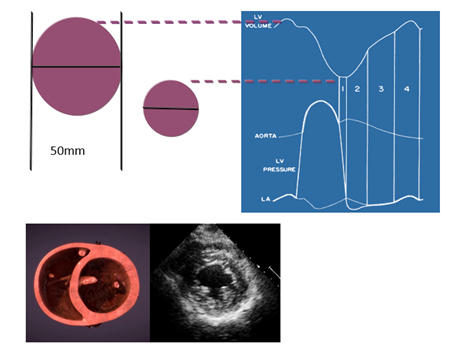

以左心室中段短轴切面为例(图7),在这个切面上,可以观察左、右心室的心腔大小,室壁厚度。左心室正常值男性55 mm,女性50 mm,正常情况下左心室和右心室横径的比例关系大约是5:2;而左心室舒张末面积(LVEDA)和左心室收缩末面积(LVESA)的比例大致是2:1。

什么叫超声容积探头围手术期经食管超声心动图监测操作的专家共识(可下载)_https://www.jmylbn.com_新闻资讯_第46张

图7 左心室短轴切面与左心室容积/面积-时间曲线的关系

左心室有两条功能曲线(图7),容积-时间曲线和压力-时间曲线,左心室容积-时间曲线的最大值点对应着左心室舒张末容积,最小值点对应着左心室收缩末容积,最大值点和最小值点之间的差值反映每博输出量(SV)。EF(射血分数)=SV/EDV。